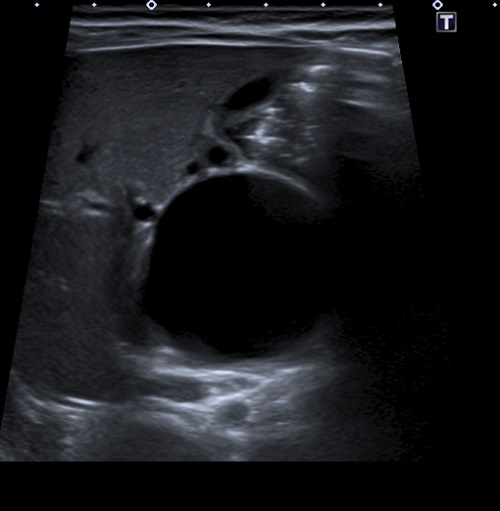

Se realiza ecografía abdominal (Fig. 1), donde se objetiva una marcada dilatación del colédoco, con morfología quístico-fusiforme, que se extiende desde hepático común hasta región pancreática, sugestivo de quiste de colédoco tipo IA según la clasificación de Todani, con barro biliar y leve ectasia de la vía biliar intrahepática. Se completa el estudio con una colangiorresonancia magnética (Fig. 2), donde se visualiza una lesión quística bien definida y redondeada del conducto colédoco en su totalidad, de 4,6 × 3,5 × 3,3 cm, sin extensión a vía biliar intrahepática, confirmando la sospecha diagnóstica inicial.